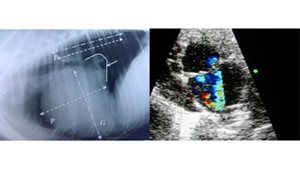

Imagerie

La clinique possède du matériel d'imagerie performant (radiographie numérique, échographie-doppler, matériel d'endoscopie) permettant de réaliser des examens approfondis et d'établir un diagnostic le plus précis possible afin de traiter au mieux les animaux.